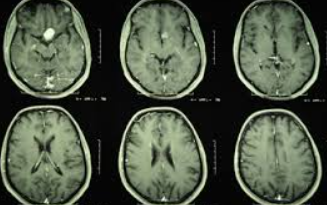

Visual acuity and visual field tests are a good screen to test for chiasmal involvement. Neuroimaging may also be needed (i.e. MRI (magnetic resonance imaging)). In some cases, endocrinologic evaluation should be considered when the cause is pituitary adenoma, which is the most common extrinsic cause of chiasmal syndrome. A pattern electroretinogram may be measured to predict the visual prognosis of patients with chiasmal compression.